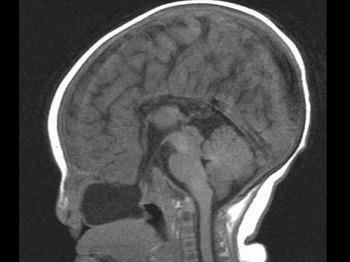

问题 两个月女婴,口咽部有一肿块,行CT检查如图,请选择最可能的诊断 ( )

选项 A、前脑无裂畸形 B、Dandy-Walker综合征 C、胼胝体发育不全 D、透明隔囊肿 E、脑积水

答案 C